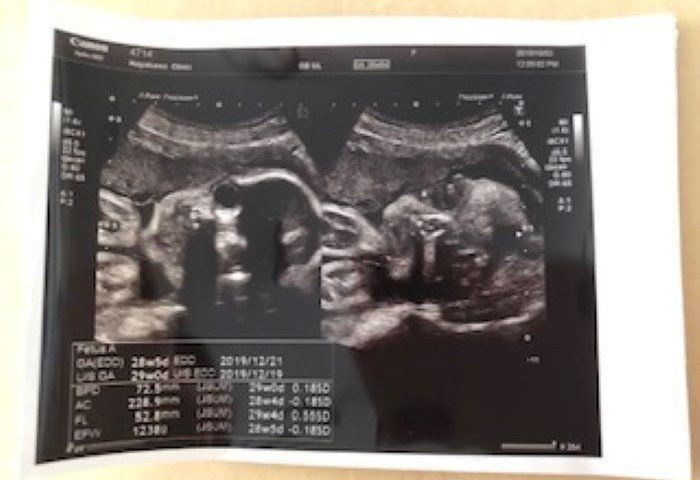

妊娠28週 どことなく長男に似ている…

28w5d 1238g

妊婦28週目。いよいよ妊娠後期に突入しました。赤ちゃんの推定体重は1238g。両手を顔の近くまで持ってくるポーズが、赤ちゃんのお気に入りのようでした。画像越しに見る赤ちゃんは、いつもこのポーズで写っていました。頭の形や横顔、顔の輪郭がどことなく長男に似ているように、私には見えました。